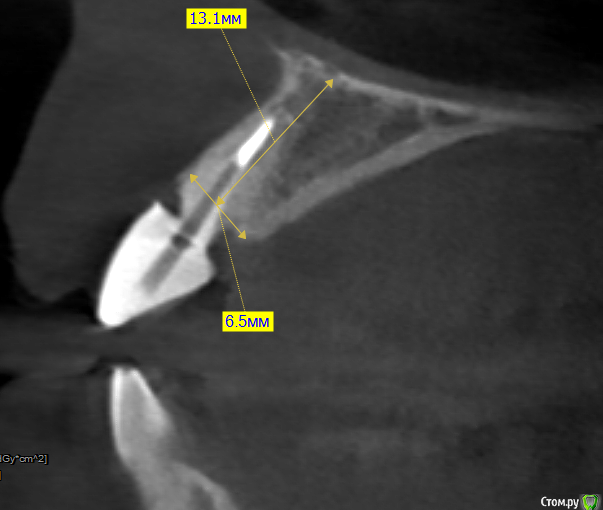

kramer Опубликовано 1 марта, 2018 Автор Поделиться Опубликовано 1 марта, 2018 Спасибо за ответы. Еще вопрос: максимум сюда влезает 12.5 мм. Каков шанс, что усилие в случае одномоментной установки будет достаточно для немедленной нагрузки, как вообще это прогнозировать? От этого ведь зависит тип временной конструкции. Ссылка на комментарий

red_butler Опубликовано 1 марта, 2018 Поделиться Опубликовано 1 марта, 2018 Еще вопрос: максимум сюда влезает 12.5 мм. 14 мм войдет, Вы же не так как делали замер, будете инсталлировать имплант 2 Ссылка на комментарий

колесников Опубликовано 1 марта, 2018 Поделиться Опубликовано 1 марта, 2018 Под винтовую другой угол. Имплант 11мм или даже 9 Ссылка на комментарий